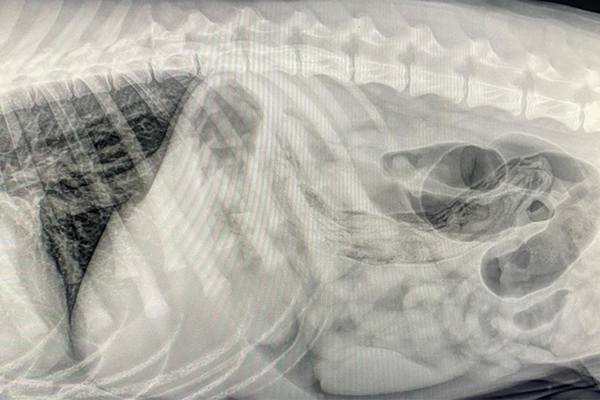

Barium Series

This procedure is a Contrast Study which means that we use a contrast dye that shows up on x-ray and highlights certain structures. Because some objects don’t show up on xray (plastic, fabric, toys, etc), this can help outline it or show us where the obstruction is as it can’t get past.

Our talented Registered Veterinary Technicians administer barium (the contrast liquid) in the mouth and then we take successive X-rays over the next few hours to watch its progress. The first X-ray is almost immediate to catch the outline of the esophagus while the last one may be hours later as it enters the colon .

Flip through the photos to see the progression of barium through the gastrointestinal tract: